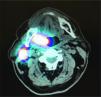

The patients were placed under an orbiter camera, and topical anesthesia (10% lidocaine) was applied to their pharyngeal mucosa. Four peritumoral injections of 40 MBq technetium-99m (99Tec) nanocolloid dissolved in 0.2 ml of physiological saline solution were administered. The first dynamic scan sequence of 60 ten-second frames started immediately after the injection. This was followed by a second sequence of 120-second frames for 30 min. In addition, 5-minute scans were conducted from the anterior and lateral aspects on both sides after 30, 60 and 120 min (Figure 1). After the dynamic scan sequences were completed and a SPECT/ CT was performed (Figure 2), the sentinel lymph nodes (SLNs) were located using a gamma probe, and their positions were marked on the skin 3,4.